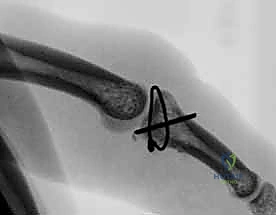

FIG 4 • A. Lateral radiograph of an unstable dorsal PIP fracture-dislocation, revealing significant volar articular surface involvement (over 50%). Such extensive involvement indicates a high degree of instability.

- V Sign: On a post-reduction true lateral radiograph, divergence of the dorsal articular surfaces from the central portion of the joint creates a V-shaped gap. This indicates an incompletely reduced joint.

- Dynamic Fluoroscopy: Extremely valuable. It allows us to dynamically assess reduction and, crucially, its stability through a range of motion. We can determine the exact joint position where instability or redislocation occurs, which guides our decision-making for conservative management (e.g., extension block splinting) or operative intervention.

- Hinged Flexion: A variant of the V-sign where congruent rotation is replaced by abnormal translation across flattened fracture segments during active flexion/extension.

FIG 4 • B. The V-sign on a lateral radiograph indicating an incompletely reduced dorsal fracture-dislocation, characterized by a V-shaped gap created by the divergence of the dorsal articular surfaces.